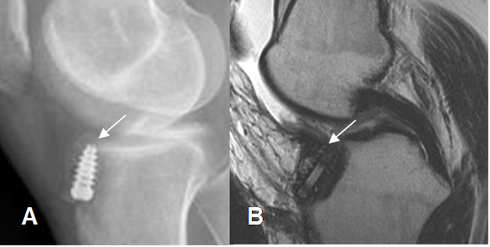

Fig 130. Túnel femoral normal.

A: Rx lateral y B: RM sagital en T1. Orientación normal del túnel femoral, en la parte posterior del cóndilo femoral.

Fig 131. Túnel femoral normal.

A: Rx AP y B: RM coronal en T1. Orientación normal del túnel femoral, dirigido hacia la 1, de las manecillas del reloj.